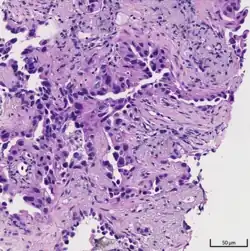

Histopathology

If possible, a biopsy of any suspected lung tumor is performed to make a microscopic evaluation of the cells involved and is ultimately required to confirm diagnosis.[7] Biopsy should be attempted in distant lesions first to establish a histologic diagnosis and to simultaneously confirm metastatic staging. The biopsy material is also used to analyze whether the tumor express any specific mutations suitable for targeted therapy (e.g. EGFR mutation or ALK mutation). Biopsy can be accomplished via bronchoscopy, transthoracic needle biopsy, and video-assisted thorascopic surgery (VATS).[4]

While sputum cytology has been shown to have limited utility, thoracentesis, or aspiration of pleural fluid with an ultrasound-guided needle, should be performed when pleural effusion is present. When malignant cells are identified in the pleural aspirate of patients highly suspect for lung cancer, a definitive diagnosis and staging (stage IV adenocarcinoma of the lung) is established.[4]

Adenocarcinoma of the lung tends to stain mucin positive as it is derived from the mucus-producing glands of the lungs. Similar to other adenocarcinoma, if this tumor is well differentiated (low grade) it will resemble the normal glandular structure. Poorly differentiated adenocarcinoma will not resemble the normal glands (high grade) and will be detected by seeing that they stain positive for mucin (which the glands produce). Adenocarcinoma can also be distinguished by staining for TTF-1, a cell marker for adenocarcinoma.[29]

As discussed previously, the category of adenocarcinoma includes are range of subtypes, and any one tumor tends to be heterogeneous in composition. Several major subtypes are currently recognized by the World Health Organization (WHO)[1] and the International Association for the Study of Lung Cancer (IASLC) / American Thoracic Society (ATS) / European Respiratory Society (ERS):[30][31][32] lepidic predominant adenocarcinoma, acinar predominant adenocarcinoma, papillary predominant adenocarcinoma, micropapillary predominant adenocarcinoma, solid predominant adenocarcinoma, and solid predominant with mucin production. In as many as 80% of these tumors, components of more than one subtype will be recognized. Surgically resected tumors should be classified by comprehensive histological subtyping, describing patterns of involvement in increments of 5%. The predominant histologic subtype is then used to classify the tumor overall.[2] The predominant subtype is prognostic for survival after complete resection.[33]

To reveal the adenocarcinomatous lineage of the solid variant, demonstration of intracellular mucin production may be performed. Foci of squamous metaplasia and dysplasia may be present in the epithelium proximal to adenocarcinomas, but these are not the precursor lesions for this tumor. Rather, the precursor of peripheral adenocarcinomas has been termed atypical adenomatous hyperplasia (AAH).[10] Microscopically, AAH is a well-demarcated focus of epithelial proliferation, containing cuboidal to low-columnar cells resembling club cells or type II pneumocytes.[10] These demonstrate various degrees of cytologic atypia, including hyperchromasia, pleomorphism, prominent nucleoli.[10] However, the atypia is not to the extent as seen in frank adenocarcinomas.[10] Lesions of AAH are monoclonal, and they share many of the molecular aberrations (like KRAS mutations) that are associated with adenocarcinomas.[10]

Signet ring and clear cell adenocarcinoma are no longer histological subtypes, but rather cytological features that can occur in tumour cells of multiple histological subtypes, most often solid adenocarcinoma.[30]